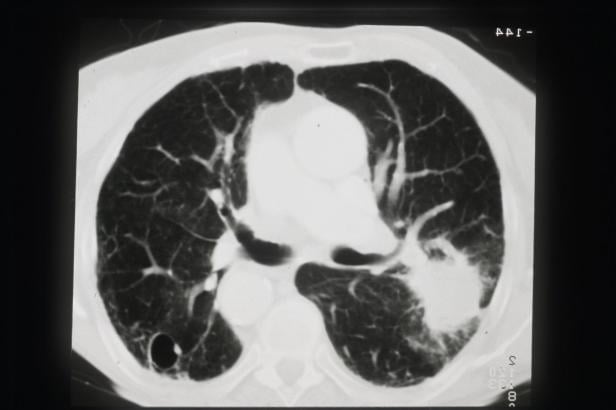

Ein CT-Scan der Lunge zeigt eine mögliche Erkrankung.